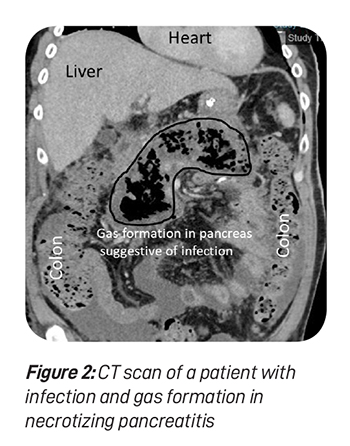

Necrosis means dead or non-viable. When a part of the pancreas or surrounding fatty tissue is dead due to severe and extensive inflammation, necrotising pancreatitis is diagnosed (see figure 1). The treatment of necrotising pancreatitis involves additional consideration for the treatment of necrotic tissue.

A bacterial sample can also be obtained by percutaneous (via skin puncture) or endoscopic-guided needle aspiration (via endoscopy). It is essential to administer appropriate targeted antibiotic treatment if infection is detected. Figure 2 shows a patient with necrotising pancreatitis with infection, evidenced by the gas formation in and around the pancreas. Targeted antibiotics are essential to reduce the development of resistant bacteria.